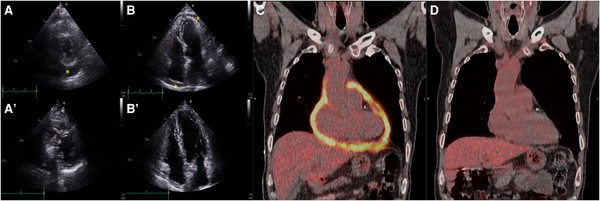

가톨릭대 서울성모병원 심뇌혈관병원 순환기내과 정미향(교신저자), 핵의학과 오주현(공동 제1저자) 교수 연구팀은 심장초음파와 양전자단층촬영(18F-FDG PET/CT)의 다학제 영상 검사를 결핵성 심낭염 초기 진단뿐 아니라 치료 경과 확인에 이르기까지 활용해 효과적으로 치료했다.

연구팀 조사 결과, 심장초음파 검사에 양전자단층촬영을 보조적으로 활용하면 환자의 심낭 내 염증 개선 정도를 정량적으로 확인할 수 있어 치료 평가에 유용했다.

결핵성 심낭염은 일반적으로 6개월간 항결핵제를 복용 후 치료를 종료한다. 그러나 염증의 충분한 개선 여부를 심장초음파만으로 정확히 알기 어려운 한계가 있었다. 양전자단층촬영을 보조적으로 활용해 치료 종료 시점의 염증 수준을 파악할 수 있다면 결핵성 심낭염 재발이나 합병증으로 인한 유착성 심막염 위험을 최소화하면서 개별화된 맞춤형 치료 전략을 수립할 수 있다.